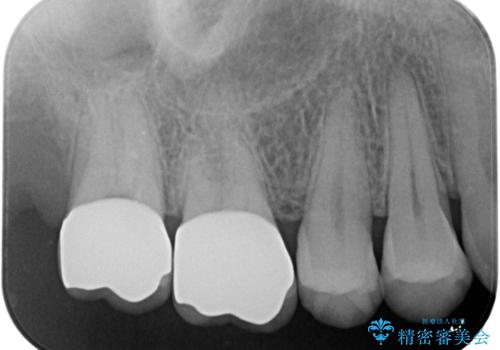

- 右上67 仮歯+ジルコニアクラウン:11,000円×2+121,000円×2 費用は治療当時の料金となります

奥歯で咬合力の負担を考慮した結果、インレーやアンレーではなくクラウンをおすすめする場合があります。